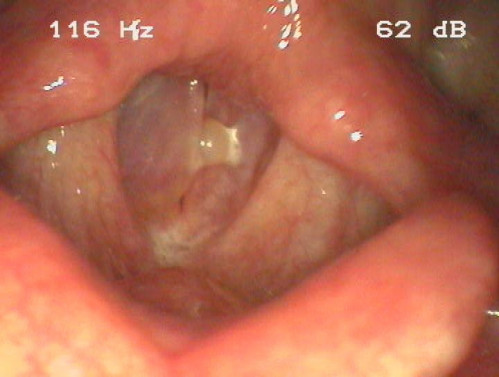

Raue, vertiefte mittlere Sprechstimme und zunehmende Heiserkeit

ICD: J38.4

Eine 47-jährige Frau beklagt eine zunehmend heisere Stimme. Die Patientin gibt außerdem an, seit ca. 30 Jahren 20 bis 40 Zigaretten pro Tag zu rauchen.

Im Anamnesegespräch fällt sofort die vertiefte mittlere Sprechstimmlage sowie eine Rauhigkeit der Stimme auf.